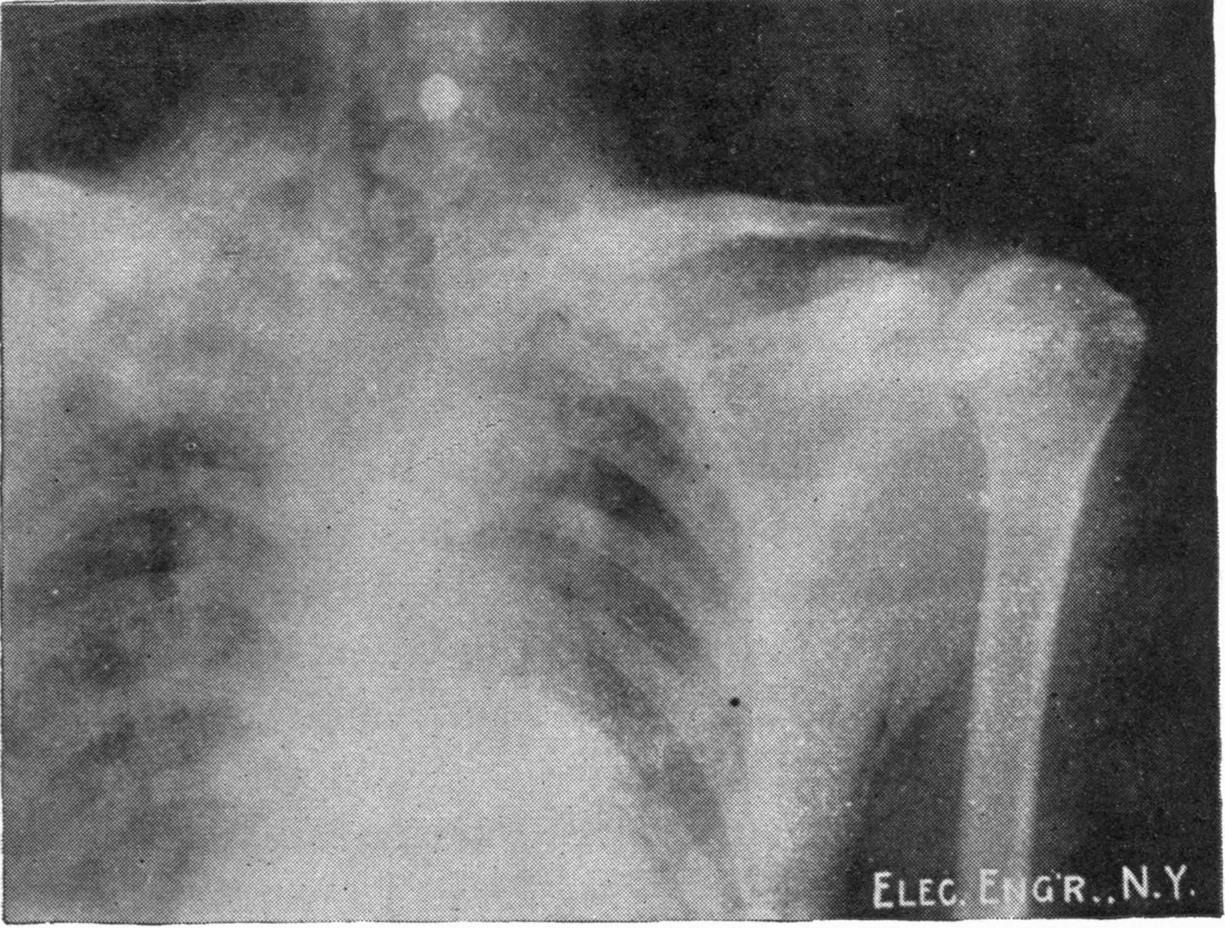

Fig. 2.—Broken Arm, Overlapping.

Fig. 3.—Ribs.

FROM SCIAGRAPHS BY PROF. DAYTON C. MILLER. § 204.

117. Transposition of Phosphorescent Spot and of Cathode Rays without a Magnet. Salvioni, Elster, Geitel, and Tesla